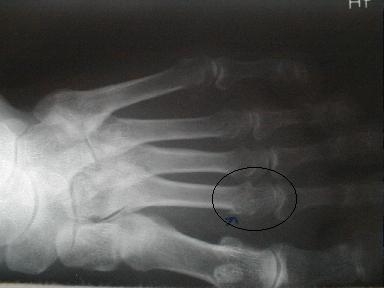

症例5

第2趾中足骨骨折

56歳 男性

負傷年日 平成11年8月6日

負傷原因 自宅でテーブルに上げてあった椅子が落ち負傷

8月6日受傷

第2中足骨骨折

皮下溢血,腫脹,圧痛、歩行痛著明

受傷時8月6日のx-pでは骨折が確認出来ずに他の医院で打撲として治療していたもので、再度x-pを撮ったところ骨折が確認できた固定をしなかった為に骨に無理な力が加わったものと思われる。固定の重要性が認識される。